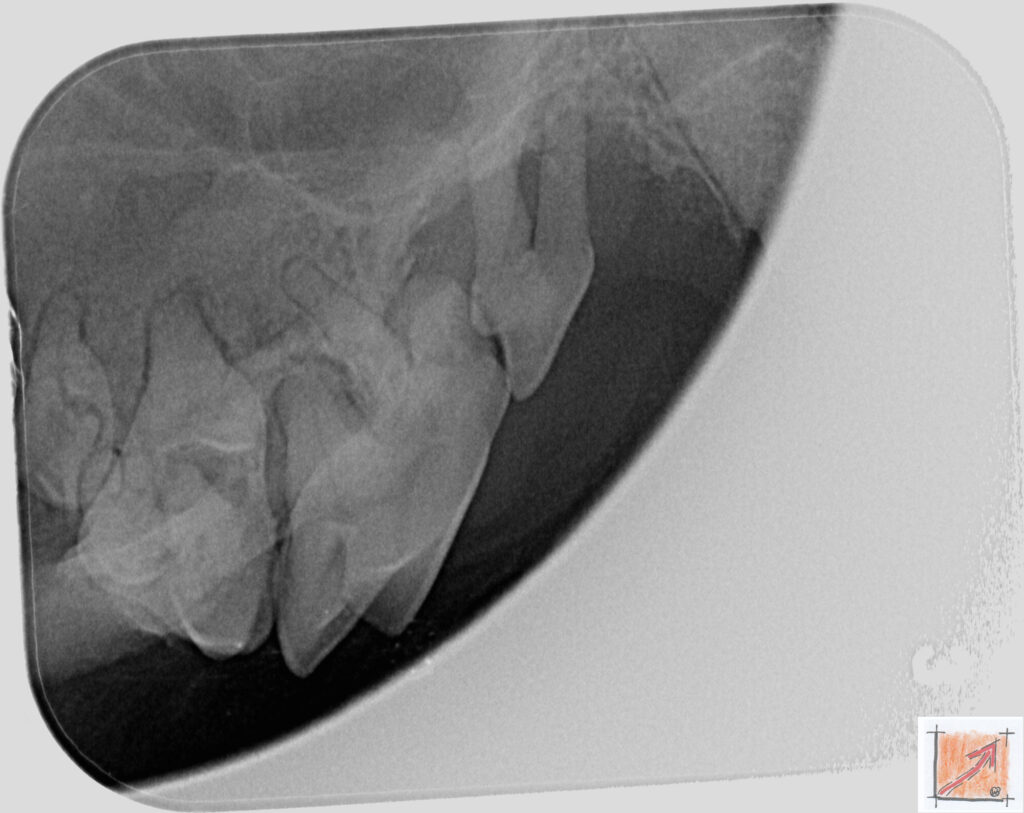

Röntgenbilder vom Thierrischen Orakel bei der Zahn-OP:

Warum Dentalröntgen beim Chihuahua lebenswichtig ist:

Ein Blick hinter die Kulissen von Chihuahua-Zähnen:

In dieser Galerie zeigen wir exklusive intraorale Röntgenaufnahmen einer Zahn-Operation beim Thierrischen Orakel als Chihuahua vom BauFachForum. Während oberflächlicher Zahnstein oft sichtbar ist, verbirgt sich die wahre Gefahr für das Herz meist unter dem Zahnfleischsaum.

Das digitale Dentalröntgen ist der Goldstandard in der modernen Tiermedizin, um parodontale Entzündungsherde und Wurzelabszesse sicher zu diagnostizieren. Für Chihuahuas wie dem Thierrischen Orakel, mit Mitralklappeninsuffizienz ist dieser diagnostische Schritt essenziell. Nur wenn versteckte Bakterienherde an der Zahnwurzel oder mit dem Fachbegriff Apikalabszesse erkannt und saniert werden, kann das Risiko einer bakteriellen Endokarditis oder einfach ausgedrückt einer Herzinnenhautentzündung minimiert werden.

Unsere Aufnahmen von Patienten dem Thierrischen Orakel verdeutlichen den Unterschied zwischen einer rein optischen Zahnreinigung und einer medizinisch fundierten Sanierung unter Röntgenkontrolle.

Chihuahua Mitralklappeninsuffizienz Trachealkollaps:

Wichtig ist im Vorfeld die Zahnhygiene des Chihuahuas. Die Bilder zeigen Dentale Röntgenbilder vom Thierrischen Orakel als Chihuahua-Hund während seiner Zahn-OP. Darstellung von Kieferknochen und Zahnwurzeln zur Diagnose von Parodontitis.

Zahnröntgenaufnahme bei Chihuahua Thierry:

Intraorales Dentalröntgen eines Chihuahuas:

Die Bilder zeigen Zähne und Wurzelstrukturen im Unterkiefer zur Planung einer Extraktion bei hochgradigem Zahnstein.